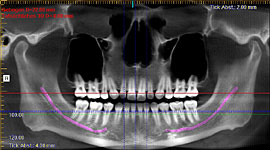

Im folgendem sehen Sie die Darstellung eines Teils des menschlichen Schädels mit Lokalisation des Nervkanales.

Orthopantomogramm (OPG) (Nervverlauf farblich dargestellt) |